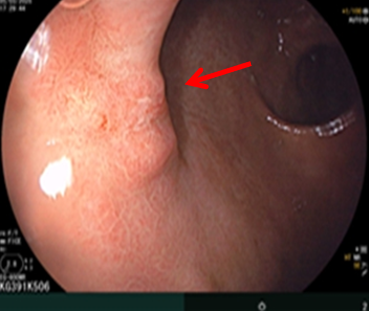

Nội soi dạ dày: Góc bờ cong nhỏ có đám niêm mạc gồ ghề, bề mặt có trợt loét kích thước ~ 1.0cm. Niêm mạc hang vị phù nề xung huyết, rải rác có vài trợt nông, và có hình ảnh viêm teo (c1), bờ teo lan tới góc bờ cong nhỏ. Góc bờ cong nhỏ có đám niêm mạc gồ ghề, bề mặt có trợt loét kích thước ~ 1.0cm.

Hình 3: Hình ảnh tổn thương tại góc bờ cong nhỏ

Sinh thiết tổn thương, giải phẫu bệnh: Ung thư biểu mô tế bào nhẫn.